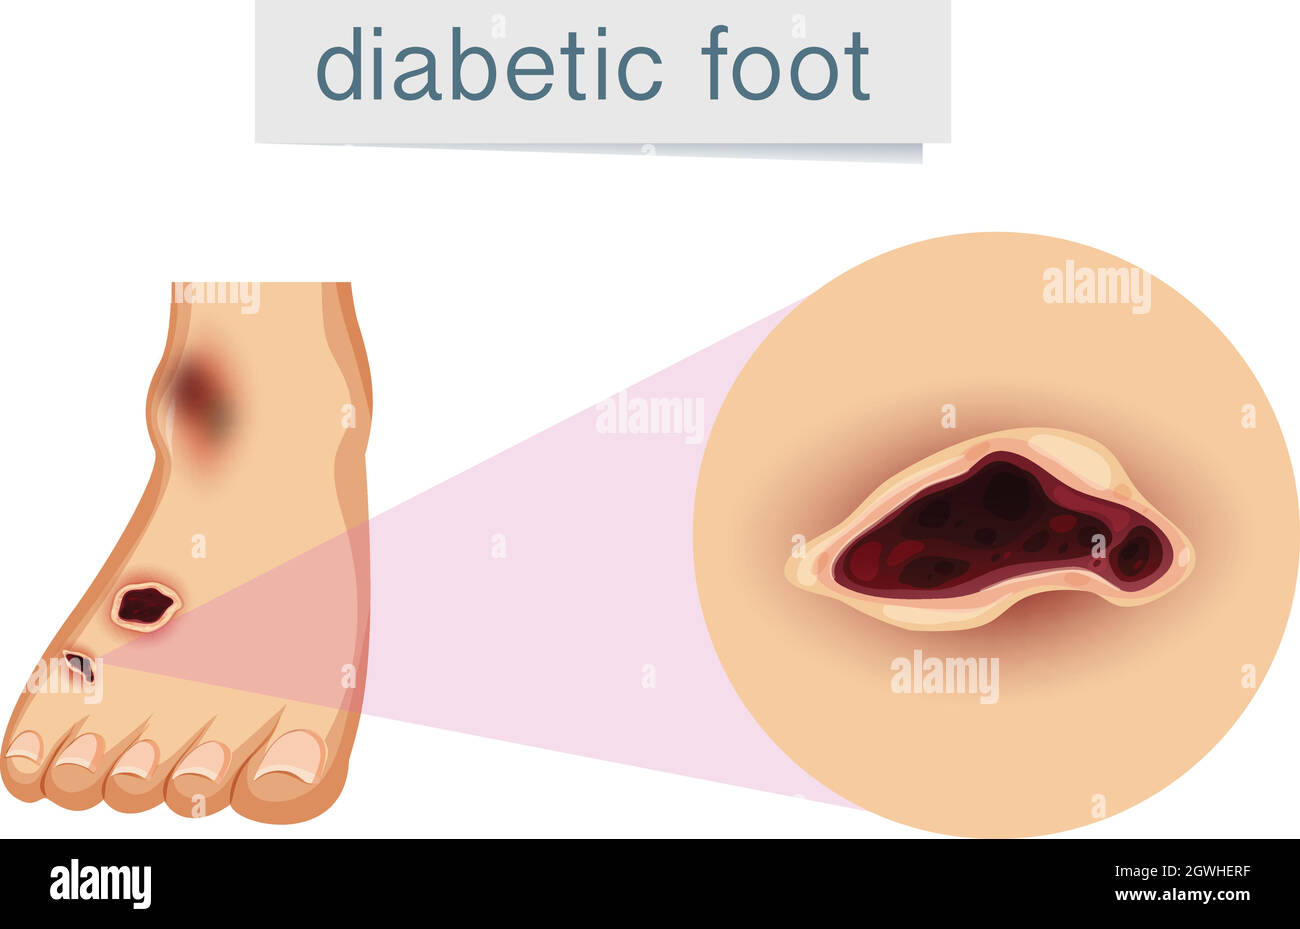

RF2DGMY46–Les verrues du pied sont causées par une infection par un type de virus du papillome humain. Gros plan du HPV